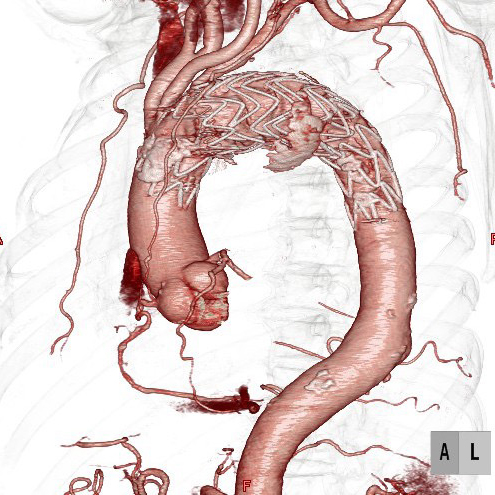

ステントグラフト挿入後CT

大動脈手術では、このシステムを利用して積極的に低侵襲治療である血管内治療(ステントグラフト内挿術)を行っています。腹部大動脈瘤だけではなく、弓部に至る胸部大動脈瘤でも、外科的処置を併用したステントグラフト治療を行なっております。